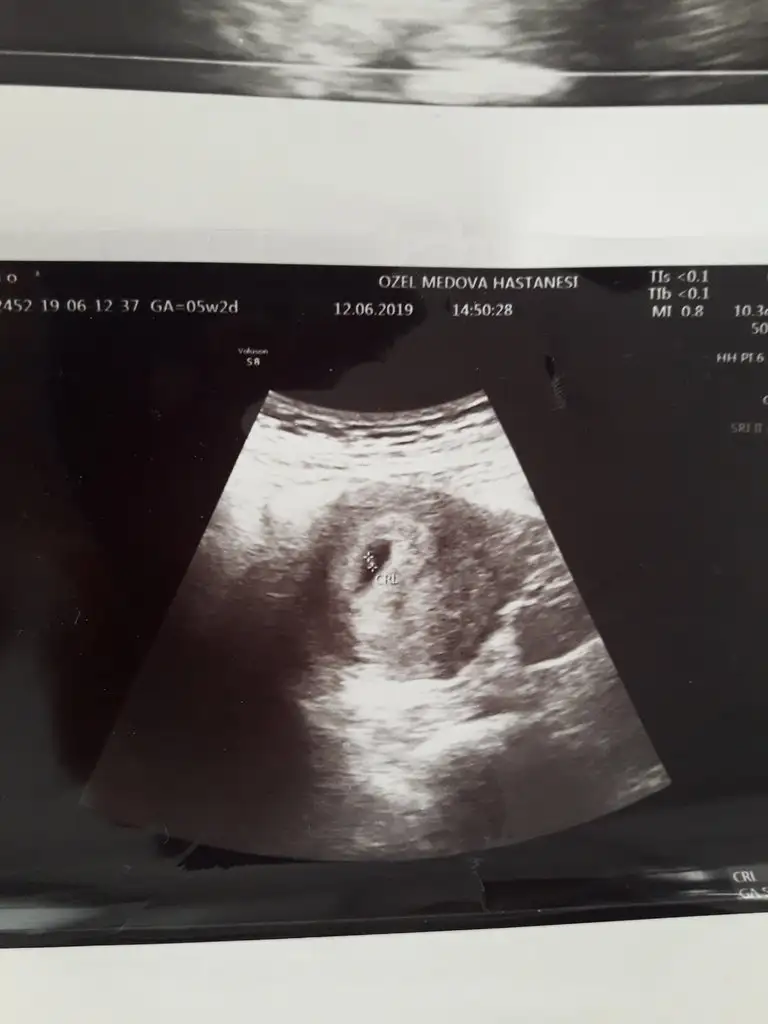

5+5 de karından gordum keseyi bebeği gormedim bile biraz da kiloluyum doktor gayet normal dedi .herkesin farklı oluyor benim gittigim zaman da kalp atisini duyanda vardir. Içini ferah tut bir de benim sat 1 mayıs senle 10 gun aramiz var bugun 7+0 oldum seninki 6 haftaliktan kuçuk olmaliEki Görüntüle 2280346

Bunu dün aldım, aslında giderken neredeyse 6 haftalık olmuştur kalbini duyabilirim diye gittim ama 4 yada 4,5 haftalık dedi doktor. Sat 11 Mayıs ve 10 Haziran'da hcg 741 çıkmıştı. Doktor üstten keseyi tam göremediği için alttan baktı ve bunu gördü sadece kalp atışını duyarız belki dedi ama kese içinde birşey görememiş çok mutsuzum şu anda. Birde ilaç kullaniyordum gyno lomexin akıntı vardı ve kaşıntı doktor fazla etki etmez ama ben olsam bunu vermezdim bebek düşünen birine dedi aklım çok karışık bel ağrısından ölüyorum. Doktora söyleyemedim bile ağrımi öyle küçük çıkınca.

Seninkinde ufak beyaz bir nokta var bu bile iyi birşey benim ki boşluk ve bel adet sancısı gibi yine de sağol desteğin için..Üzülme kuzum bende 5hafta 2 günlük gittim aynı bu şekilde sadece kese gördüm ve alttan aynı seninki gibi bana da kese kenarda dedi içe doğru büyümesi gerekiyor dedi...yarın doktora gidecem 6hafta 2günlük oluyor bakalım ben görebilecek miyim...bak benimde ultrason görüntün bu şekilde seninkine çok benziyor..